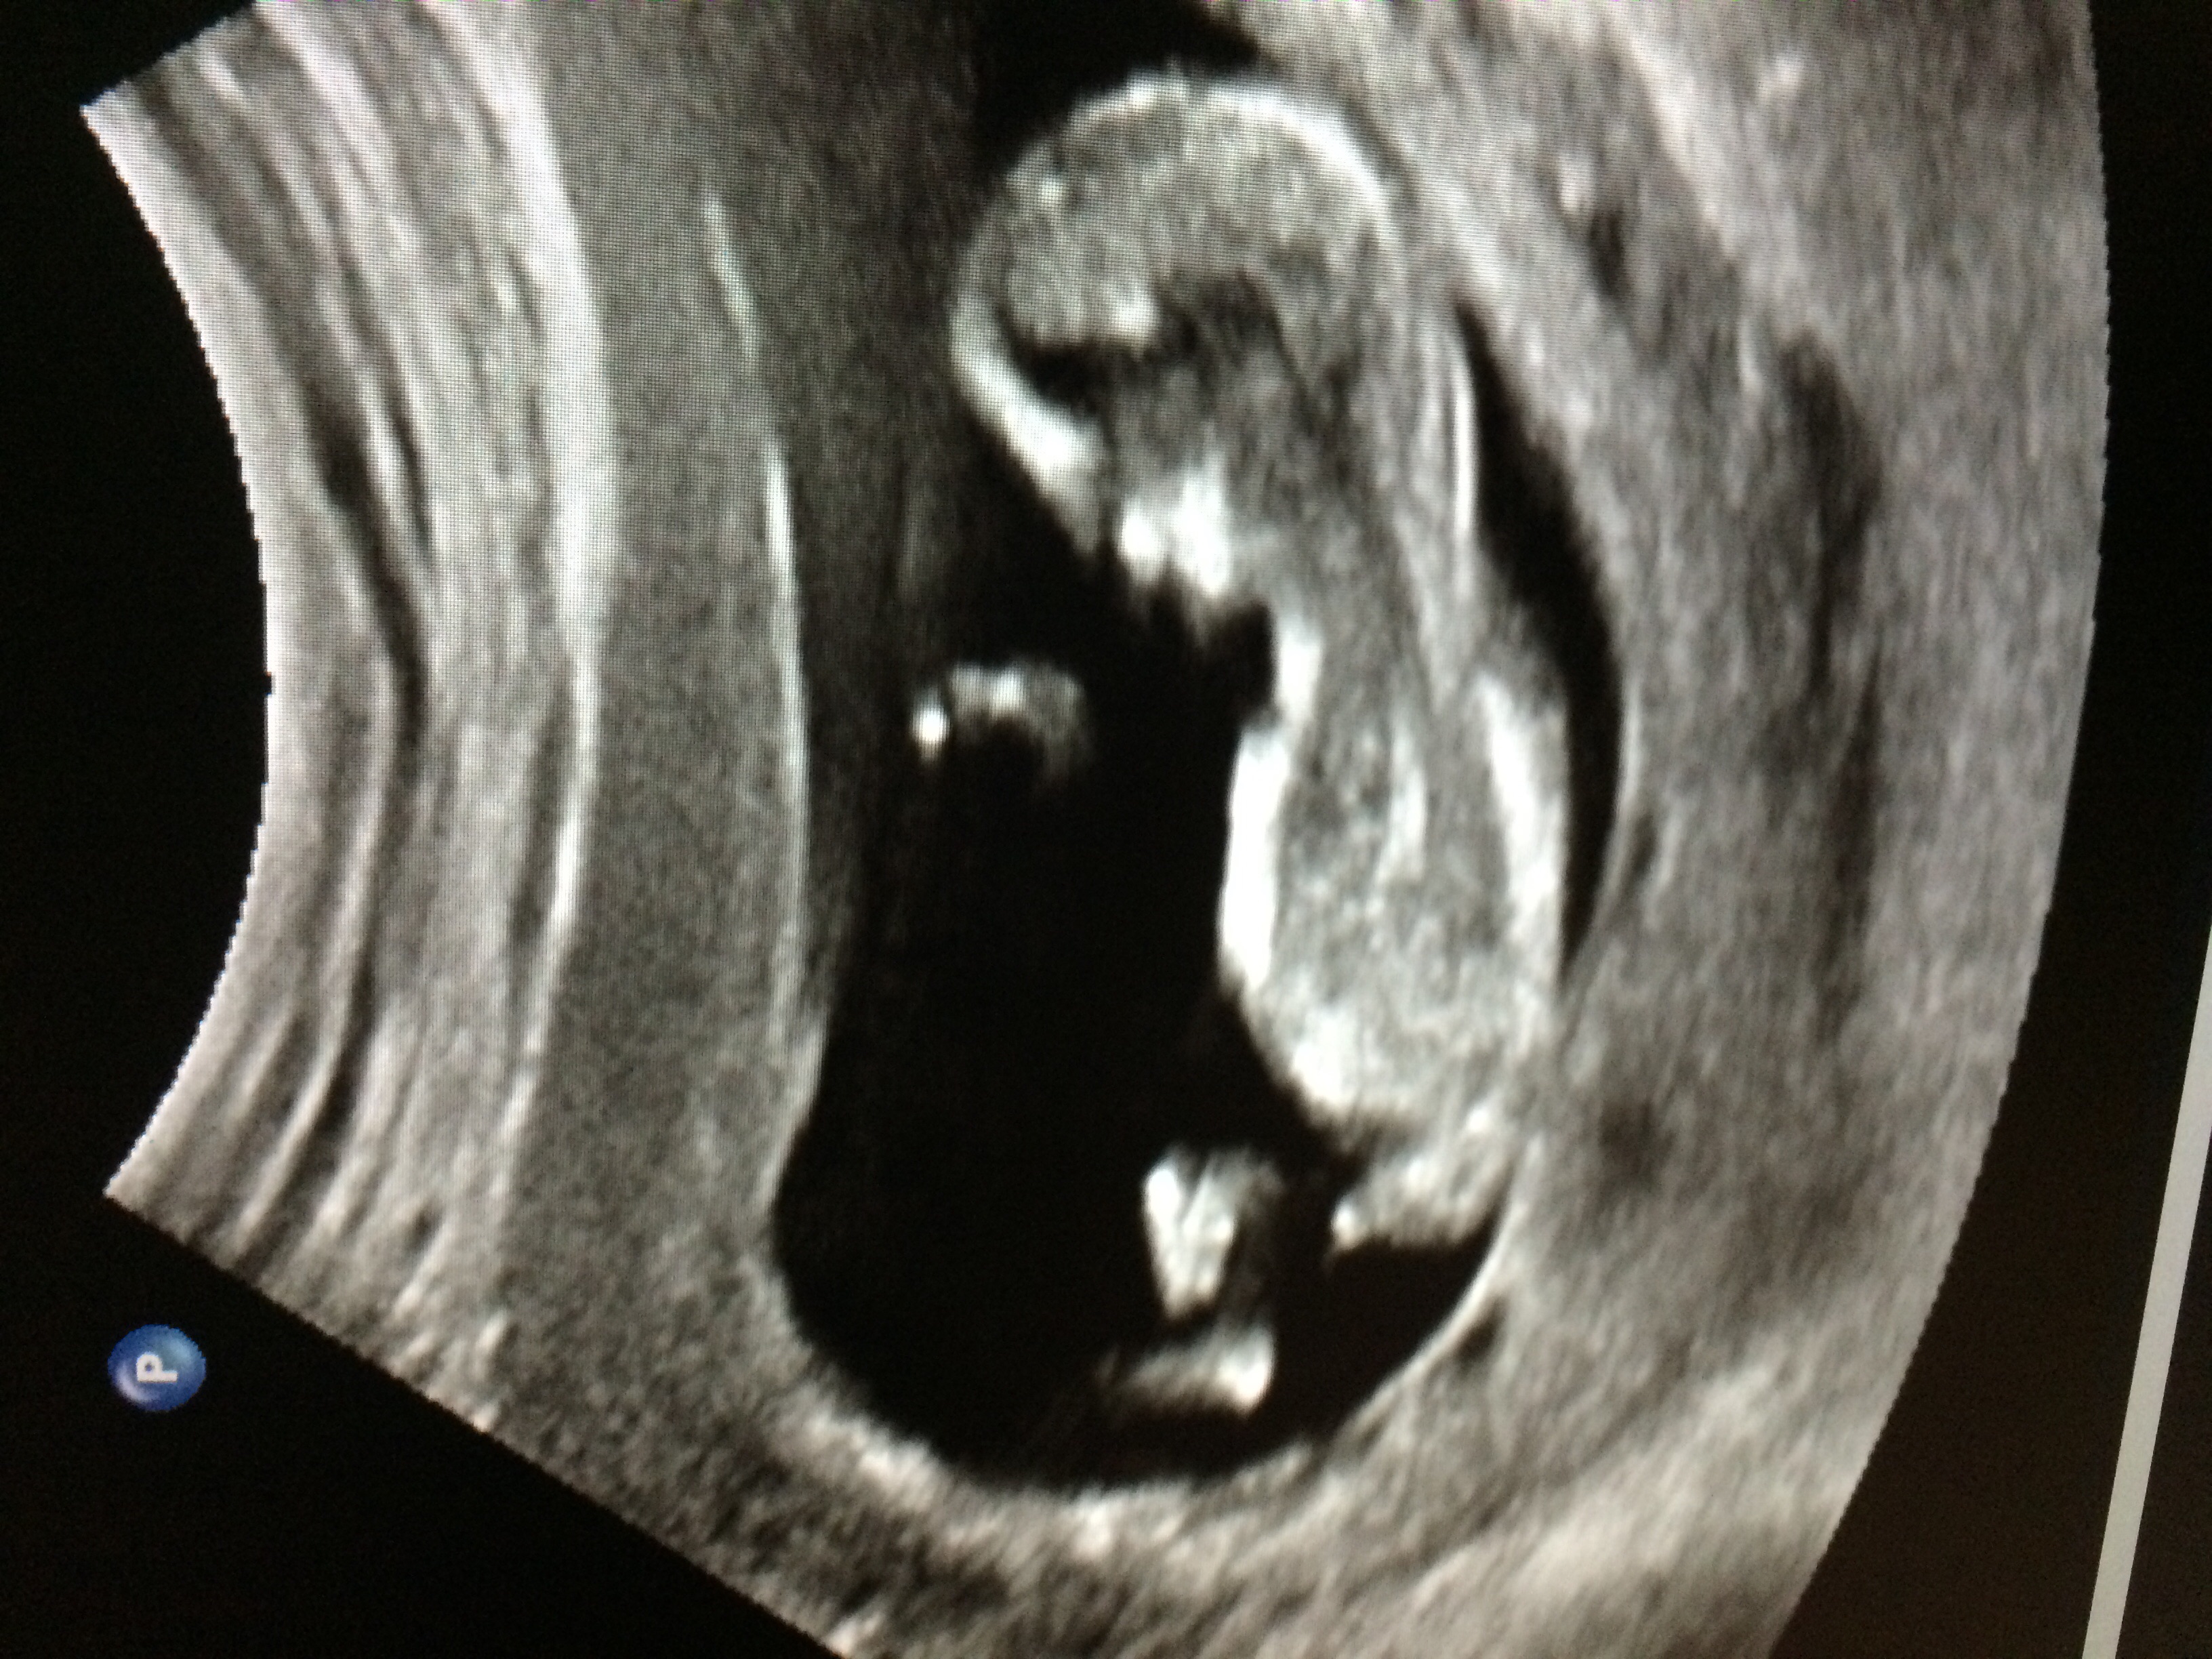

i would say boy x

Definitely boy

Boy

These are all same baby lol between 12-12/6